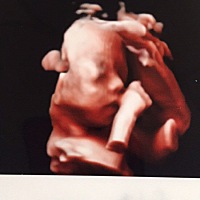

宝宝3个月12天

宝宝105天